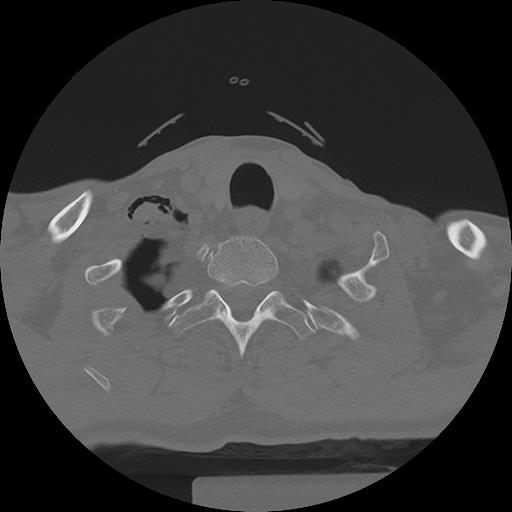

11 HUESO,,Axial,2.0,HUESO,,